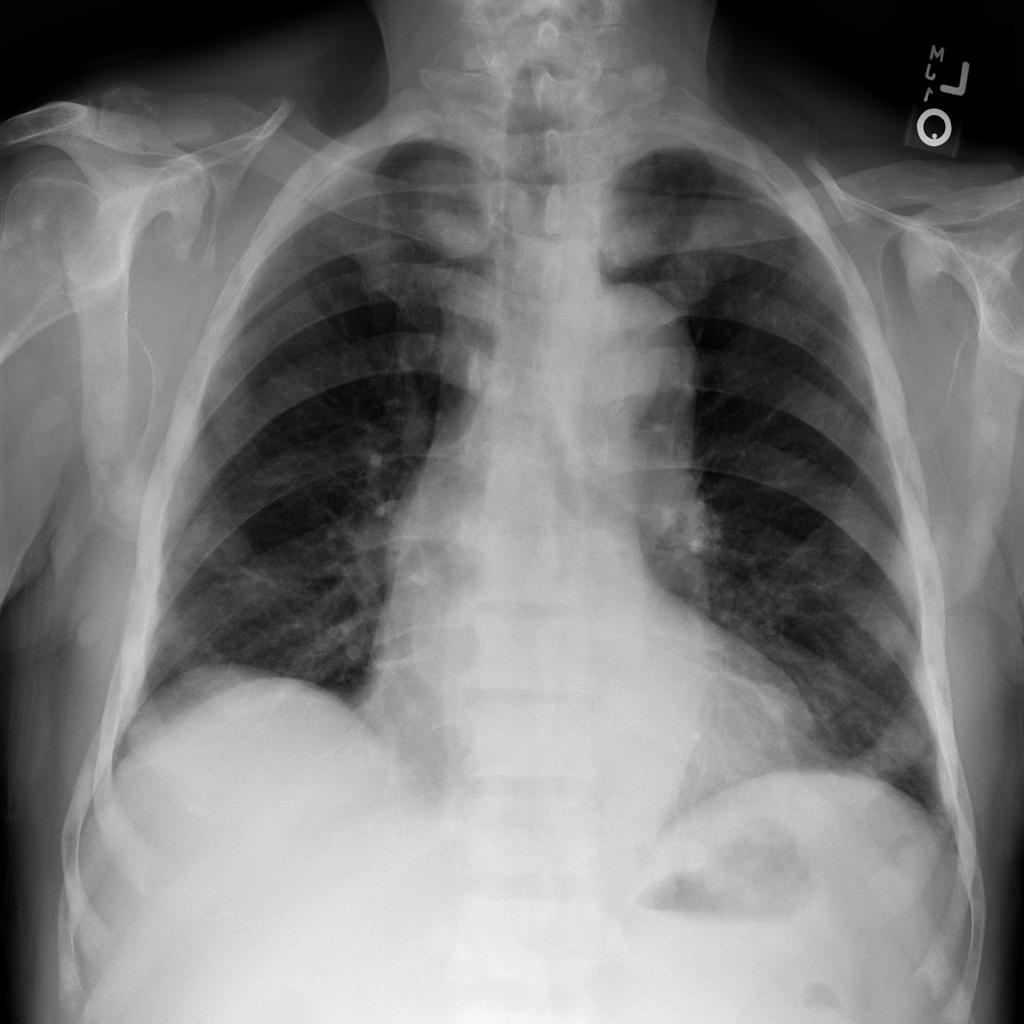

PAT-86C8 · IMG-000Effusion

PAT-86C8 · IMG-000

PA